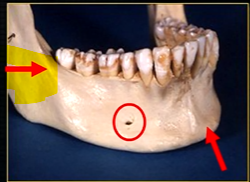

mandible - the lower jaw

mental foramina

anterior lingual/inner aspect of the mandible

bony spurs

genial tubercules - muscles of the tongue and neck attach here

lingual pit

mylohyoid ridge - mylohyoid attaches to form the floor of mouth

mental nerve - coming out of the mental foramen

mental foramen - black radiolucency - near 1st and 2nd premolars